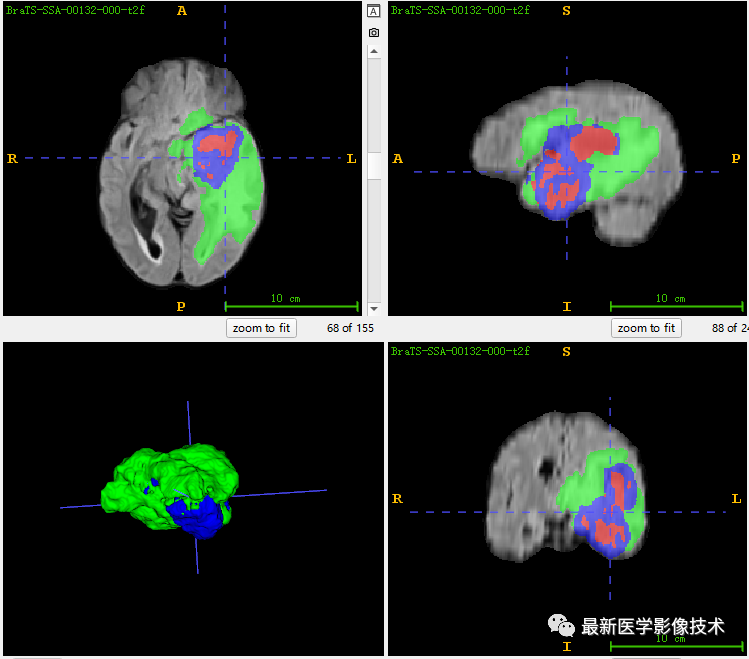

7、测试集分割结果